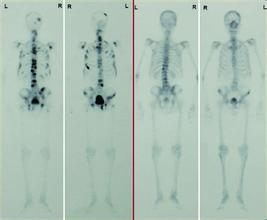

骨扫描骨转移

肺癌骨转移骨扫描图片

骨扫描骨转移报告图

骨扫描显示骨转移图片